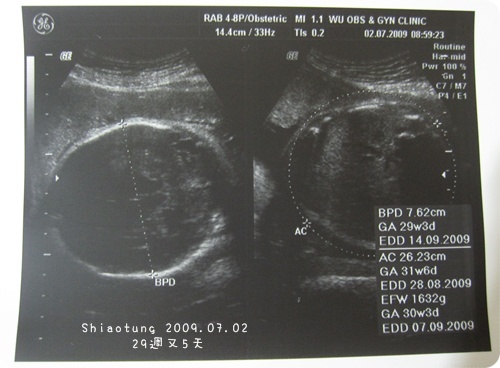

教你們看下面的照片喔...

左邊BPD是頭圍,

目前7.62cm,這要很care,不然太大會很難擠出來

預估出來跟我實際週數差不多,

GA約29w3d,

所以很標準!

AC是寶寶肚圍,

這就是看寶寶體重大概多少,

上個月不到850g,

這次足足約1632g,

我真的有驚到!!

可是醫生有拉比較大一點的肚圍啊...

你們看、你們看,虛線是不是大於寶寶肚子?真的很愛計較,胖孕婦的辛酸